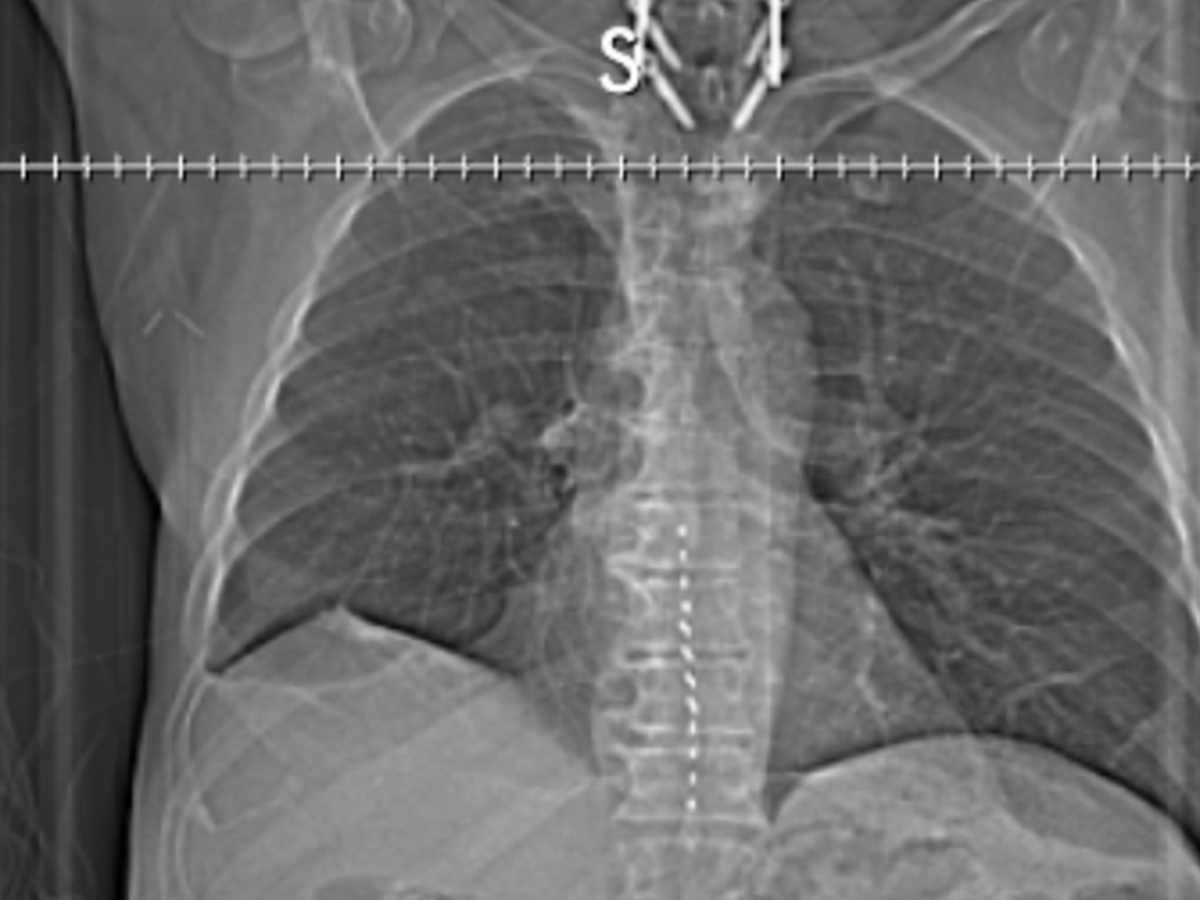

However, I have also been diagnosed with lung cancer that has spread locally to the thorax. It is considered locally spread, a Stage III diagnosis. The doctors believe there is a 20-30% chance of a cure with treatment, and we are committed to moving forward with the plan.

The most challenging chapter of my life began in August 2024, with a diagnosis of heart disease that required three stents. In November 2024, the situation escalated with a diagnosis of Large Cell Neuroendocrine Carcinoma Lung Cancer. Following a partial lung and lymph node removal in February 2025, we were overjoyed to hear that the lymph nodes were clear of cancer. We had hope that the Cancer was gone.

Unfortunately, in August 2025, the cancer returned aggressively, metastasizing to my thorax. Further imaging has shown new growths, so I am scheduled for more biopsies on October 31, 2025, to check if it has spread to my liver. My oncologist has given me a prognosis of 6 to 8 months without treatment. My current treatment plan is an intensive combination of chemotherapy and radiation, if the new growths are not more cancerous.